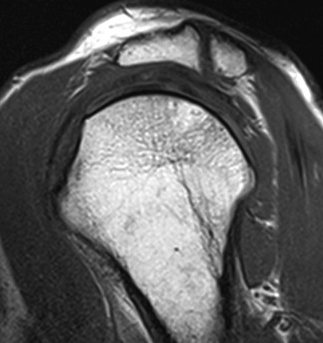

Axial MRI Sagittal MRI

MRI

Useful investigation - may show edema if problematic / mobile / causing pain